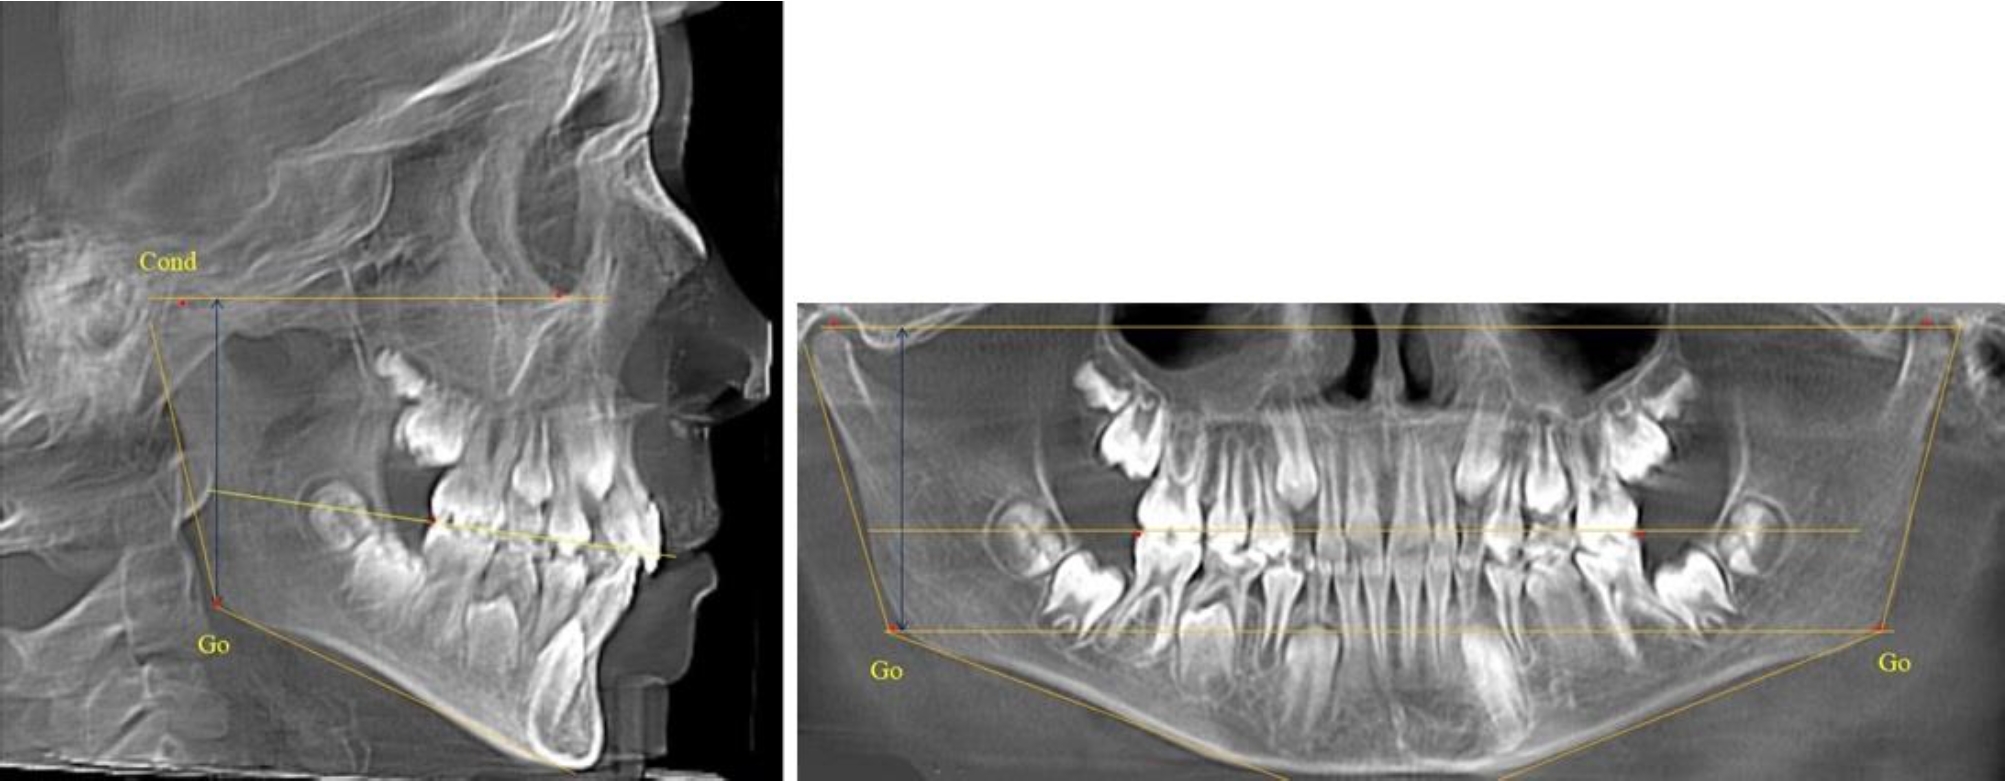

В 1-й группе были проанализированы 7 телерентгенограмм и 7 ортопантомограмм, что составило (6,60 ± 2,41) % от числа изученных рентгенограмм. На всех парах рентгенограмм угол нижней челюсти, измеренный на телерентгенограмме, соответствовал углу, полученному при построении угла на ортопантомограмме. Окклюзионная линия практически однотипно делила ветвь на два отдела (рис. 1).

Как на ортопантомограмме, так и на телерентгенограмме высота ветви у детей в периоде сформированного прикуса молочных зубов составляла (42,21 ± 2,48) мм. При этом высота верхней окклюзионно-суставной части была (22,57 ± 1,46) мм, а нижней – (19,64 ± 1,54) мм.

Учитывая вариабельность абсолютных величин, определи относительные показатели соразмерности частей ветви нижней челюсти. Так, отношение высоты верхней части ветви к нижней в среднем составляло 1,15 ± 0,13. Отношение общей высоты ветви к верхней ее части составляло 1,87 ± 0,14, а отношение общей высоты ветви к нижней ее части было 2,14 ± 0,16 и достоверных различий по относительному показателю отношения всей высоты к верхней и нижней челюсти нами не отмечено (р ˃ 0,05). При этом визуально обе части выглядели примерно равноразмерными.

На всех парах рентгенограмм угол нижней челюсти, измеренный на телерентгенограмме, так же, как и в 1-й группе, соответствовал углу, полученному при построении угла на ортопантомограмме. Окклюзионная линия делила ветвь на два отдела (рис. 2).

Рис. 1. ТРГ и ОПТГ пациента 1-й группы

Рис. 2. ТРГ и ОПТГ пациента после прорезывания первых постоянных моляров